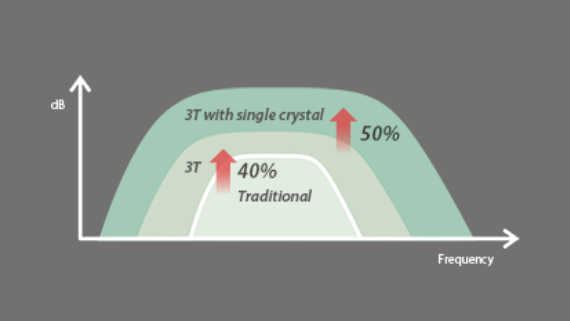

Fortgeschrittener Echo-Boost

Mindrays konsekutiver Durchbruch hin zu allerbester Ultraschall-Bildgebung.